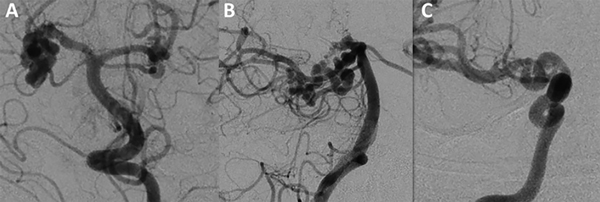

Para definir a estas malformaciones los autores mantienen la descripción original de McLaughlin1 et al de 2013: son arterias dilatadas, superpuestas y tortuosas que forman una masa de asas arteriales con una apariencia similar a un resorte en ausencia de cualquier componente venoso asociado (ver figura 1).

FIG. 1 Mujer de 20 años que se sometió a una evaluación de TAC de cerebro sin contraste después de un trauma. Las angiografías cerebrales demostraron un segmento P2 de la arteria cerebral posterior derecha e izquierda fuertemente enrollado y moderadamente tortuoso (A y B) y un segmento supraclinoideo moderadamente tortuoso y ligeramente enrollado de la arteria carótida interna derecha (C). Imagen tomada de la publicación comentada.